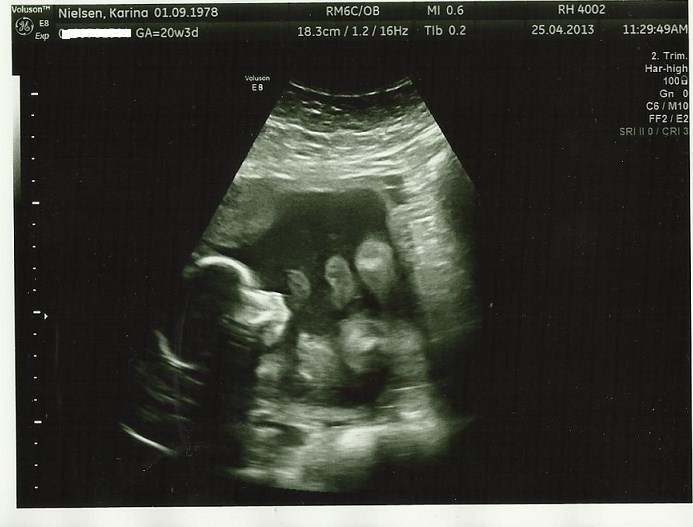

Vi har været afsted og se til lillefisen i dag 19+4 - 30. min hvor jeg var helt væk i skærmen, så jeg glemte helt at spørge om vægt osv.

Nå, det hele gik super fantastisk! En helt igennem sund og rask baby - lillefisen havde dog valgt ikke at ligge som scanningsdamen ville, men hun kom med et bud på et køn - en lillebror til Isabella

Haha prøv lige at se nogle aliensbilleder vi fik med hjem denne gang